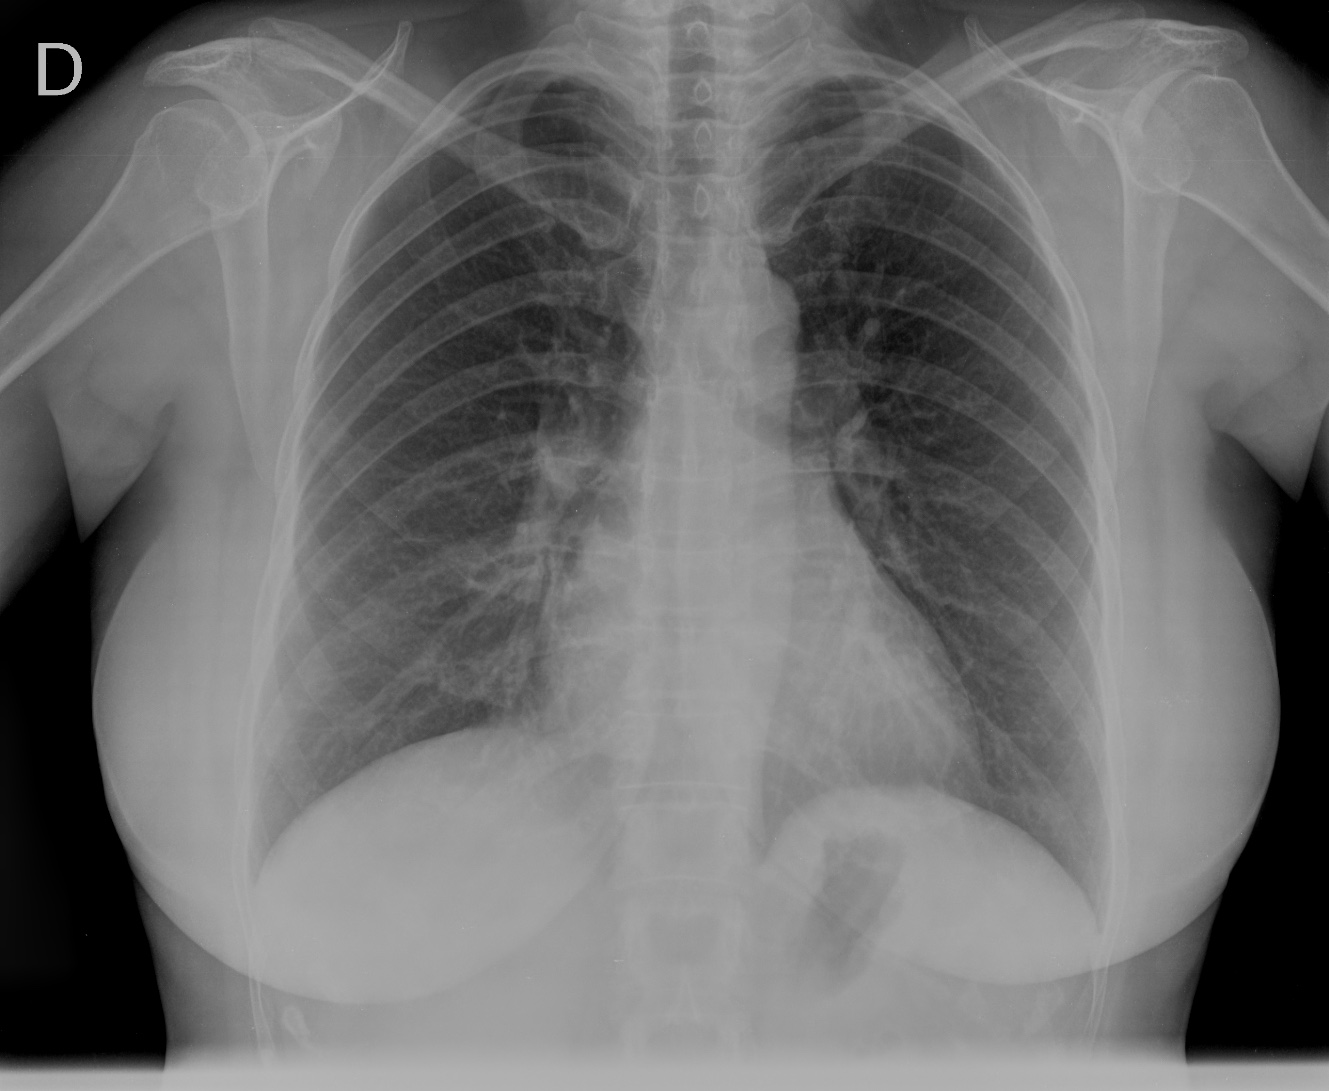

CASO: Operada de esofaguectomia y reconstrucción con coloplastia hace 3 meses. Sintomas de neumonía.

Hallazgos:

- De inicio llama la atención una densidad practicamente total del todo el hemitórax izquierdo, lo cual podría hacernos pensar que estamos ante una posible neumonía.

- Sin embargo el tórax está no está bien centrado, observar como la clavícula izquierda se encuentra casi en la mitad del pulmón, por tanto lo que vemos blanco es el mediastino ya que el tórax está rotado.

CENTRAJE:

El correcto centraje se determina comprobando que las extremidades internas de ambas clavículas equidistan de las apófisis espinosas vertebrales.

Mismo paciente, al cual esta vez se le ha tomado una radiografía en PA y en sedestación. Observar como las clavículas están equidistantes a las apófisis espinosas y como ha desaparecido el velamiento del pulmón izquierdo.

Por otra parte, paciente presenta una cardiomegalia y un discreto ensanchamiento del mediastino es probable relación con cambios postquirúrgicos.